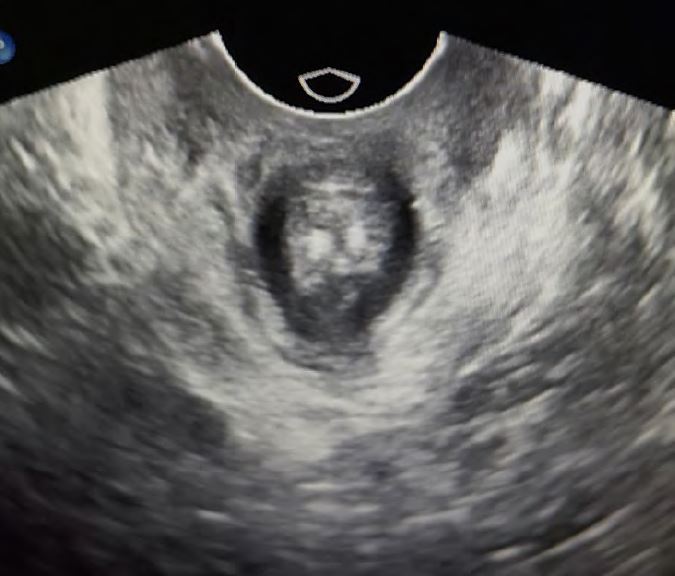

Pic. 5: Midline Zystocele

It is also possible to observe the longitudinal movement of the pelvic floor. Especially dorsal, this indicates a high risk of recurrence for posterior defects. On the one hand, the stability of the pelvic floor muscles can be palpated well, especially the ability of the patient to actively control the muscles is very easy to check with palpation, but ultrasound can also visualize the concentric work of the muscles very well. This helps, above all, the patient to observe the activity of the muscles herself. This works very well with a normal vaginal probe. With ultrasound, an avulsion (rupture of the levator muscle) can be well excluded or confirmed (Pic.:2).

Ultrasound provides the examiner with a dynamic view of the pelvic floor. Perineal sonography can be performed with a curved array, but a vaginal probe is also very suitable for imaging the pelvic organs. It is particularly valuable to see the situation and relationship of the organs in normal position, but also in motion. The patient should be instructed to press in different strengths, but also to cough repeatedly. Thus, the bladder neck and bladder bottom can be displayed very well. Midline defect can be easily seen and the wall thickness of the anterior vaginal wall can be assessed very well.